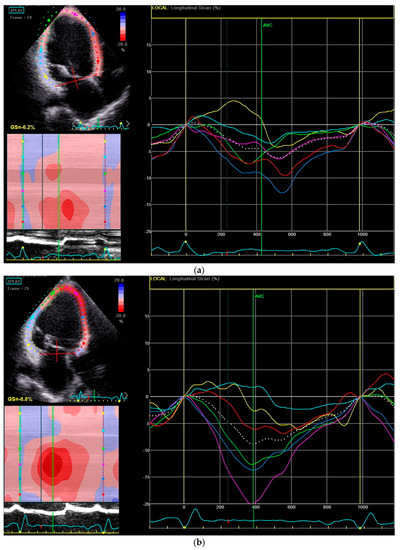

| Global longitudinal strain (%) | −7.0 ± 2.6 | −8.9 ± 2.8 | 0.001 |

| Mechanical dispersion (ms) | 88.4 ± 28.1 | 78.1 ± 26.1 | 0.036 |